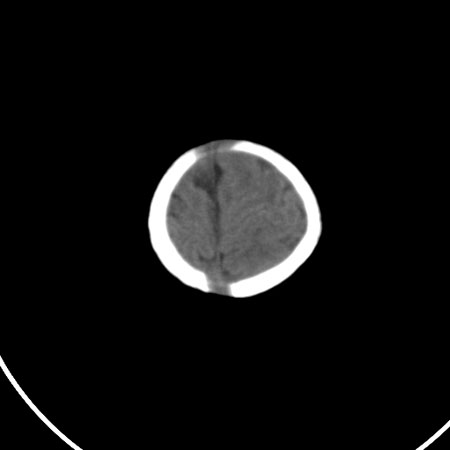

以下是引用小初学者在2009-1-10 17:51:00的发言:[br]考虑缺血缺氧性脑病后遗性改变。

以下是引用拾荒者在2009-1-10 19:23:00的发言:[br]生后有蛛网膜下腔出血病史,现幕上脑室明显扩张,脑室周围白质局限性密度减低,考虑hie脑病后遗表现。